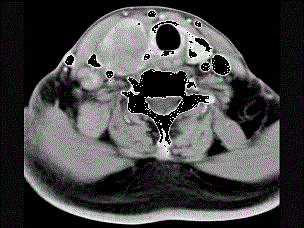

问题 女性,54岁,右侧颈部肿大近1年,近来病人有声嘶、吞咽困难,CT扫描如图,请选择正确的描述和答案 ( )

选项 A、考虑甲状腺癌 B、右侧颈内静脉瘤栓形成 C、增强扫描示甲状腺呈不规则强化团块影,其内有低密度区,病灶境界不清 D、右侧颈内静脉增粗,其内可见不规则充盈缺损区 E、右侧甲状腺肿大,密度减低

答案 ABCDE